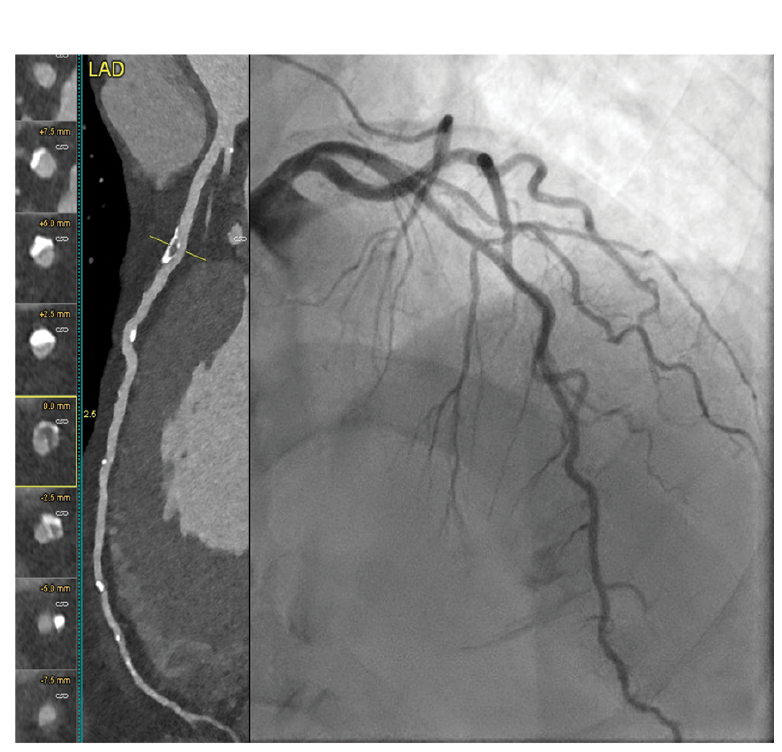

Images/courtesy WellSpan Heart & Vascular Institute

The RCA (Figure 2) demonstrated a patent stent but severe stenosis in the native artery (Figure 3) at the stent’s distal segment. Severe stenosis was noted in the Cx (Figure 4) proximal to the previously placed stent. CCTA findings were confirmed by invasive angiography. A diastolic hyperemia-free ratio (DFR) across the lesion in the LAD was abnormal at 0.89. The patient later received intravascular ultrasound-guided PCI of the Cx, LAD, and RCA.